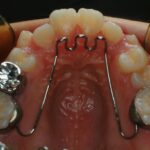

수술교정

교정치료만으로는 해소가 안될 만큼 위, 아래턱의 부조화가 너무 심한 경우를 방치하면 턱관절에도 심각한 영향을 주므로 교정치료 중간에 양악 수술을 같이 진행하여 외모 개선 및 기능을 찾아줍니다.